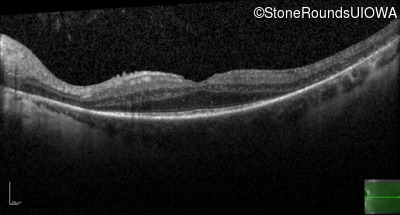

Age at visit: 37 years

OD OS